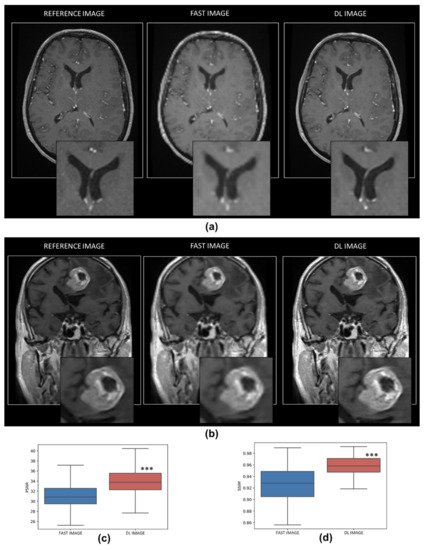

3.1.1. Quality of the Resampling DL Model

3.2.1. Quality of the Denoising DL Model